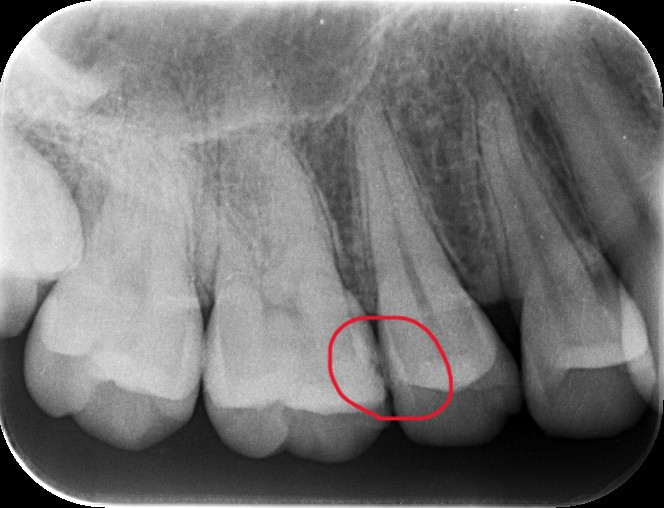

上の写真が処置した部位なります。写真からは、間に黒い部分があるのが見えると思いますが、レントゲン上ではどうでしょうか?

問題の部位は、ここになります。はっきりしたものは映っていません。では、その部分の実際はどうだったのかというと・・・

古いつめものの下の部分も含め、かなりの範囲に広がっていました。それよりも問題なのは、一番最後の写真に写っている削った部分の茶色い部分は、ほぼ神経の真横、ということです。そこまでの大きさなのかは、処置前には全く分かりませんでした。